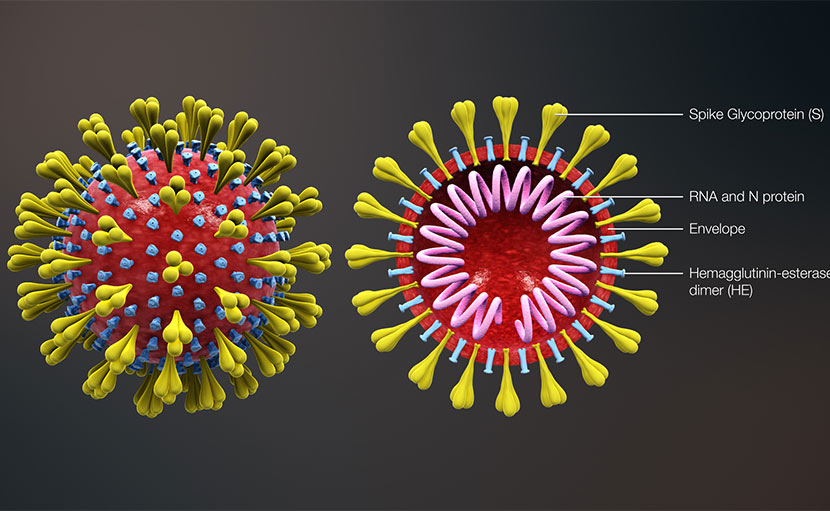

করোনা ভাইরাস । সচেতন থাকুন এখন থেকেই!

0 SHARES Share Tweet ইলেক্ট্রনিক ও প্রিন্ট মিডিয়ায়, ফেসবুকে এবং অন্যান্য সামাজিক যোগাযোগ মাধ্যমে এ সময়ে সবথেকে বেশি আলোচ...